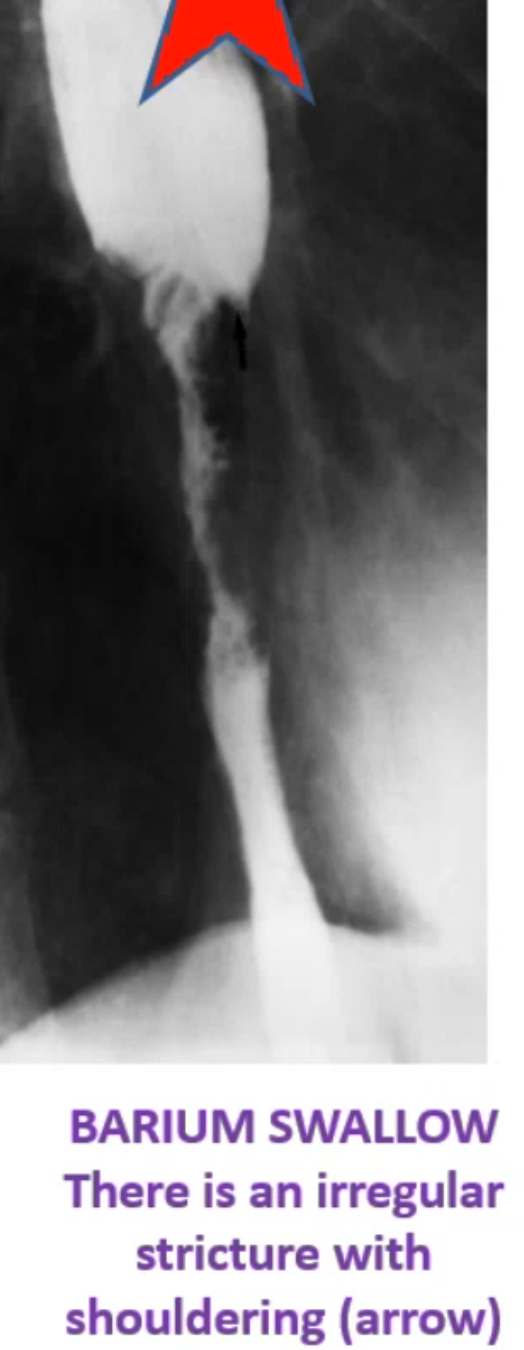

Malignant stricture DYSPHAGIA:

produce abrupt narrowing. It is irregular and associated with mucosal destruction. Z